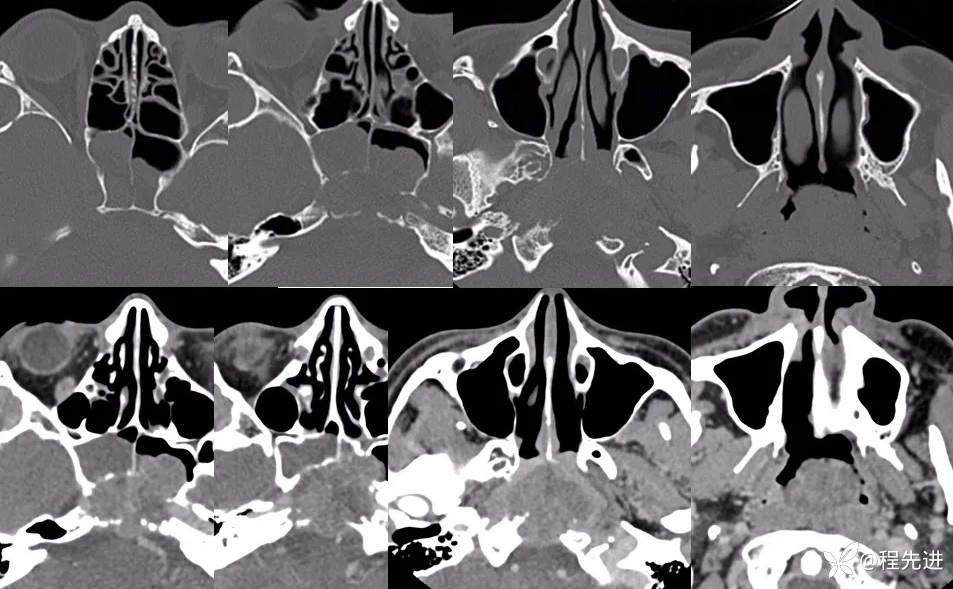

CT增强: